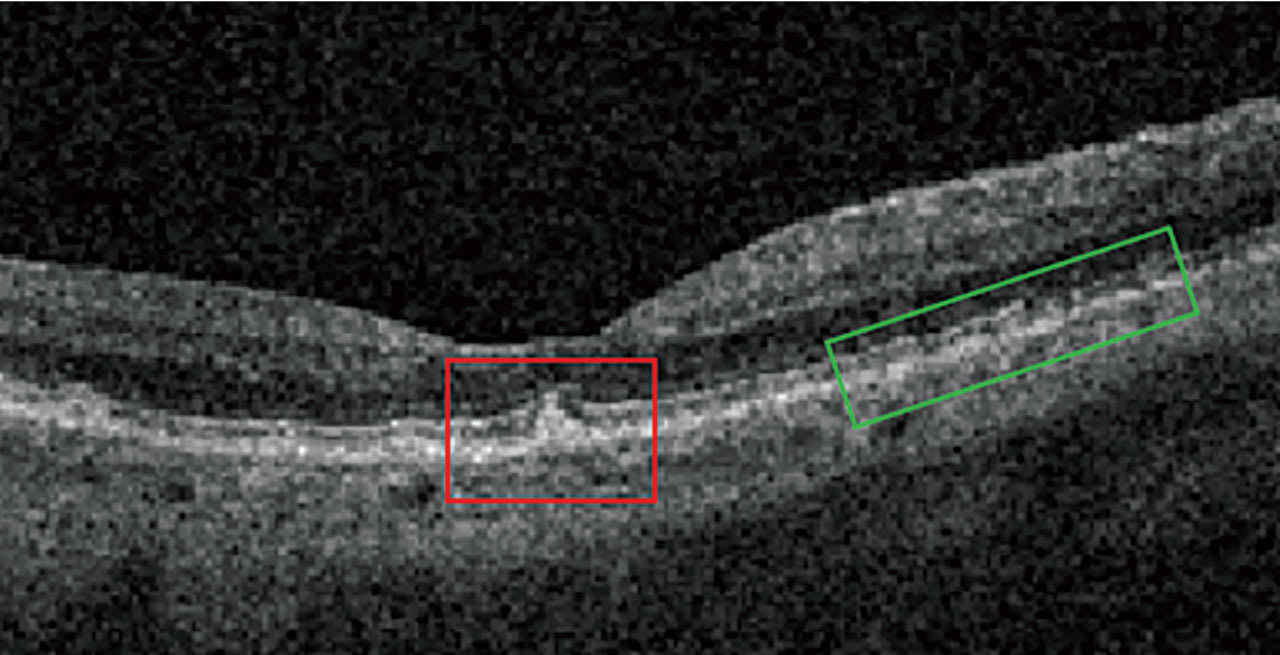

Nascent GA is drusen-associated incomplete RPE and outer retinal atrophy (iRORA) without CNV.1,2 On OCT, it appears as a subsidence of the outer plexiform layer (OPL) and the inner nuclear layer (INL), along with a wedge-shaped band within the OPL.1 The lesion’s boundaries are defined by “an abrupt increase in choroidal reflectivity below Bruch’s membrane; the RPE, photoreceptor, and choriocapillaris layer loss; and external limiting membrane absence/descent”.1 Also, nascent GA and iRORA increase progression risk to GA. In fact, eyes that have some of the findings of iRORA are at high risk of developing advanced AMD3 (Figure 2).